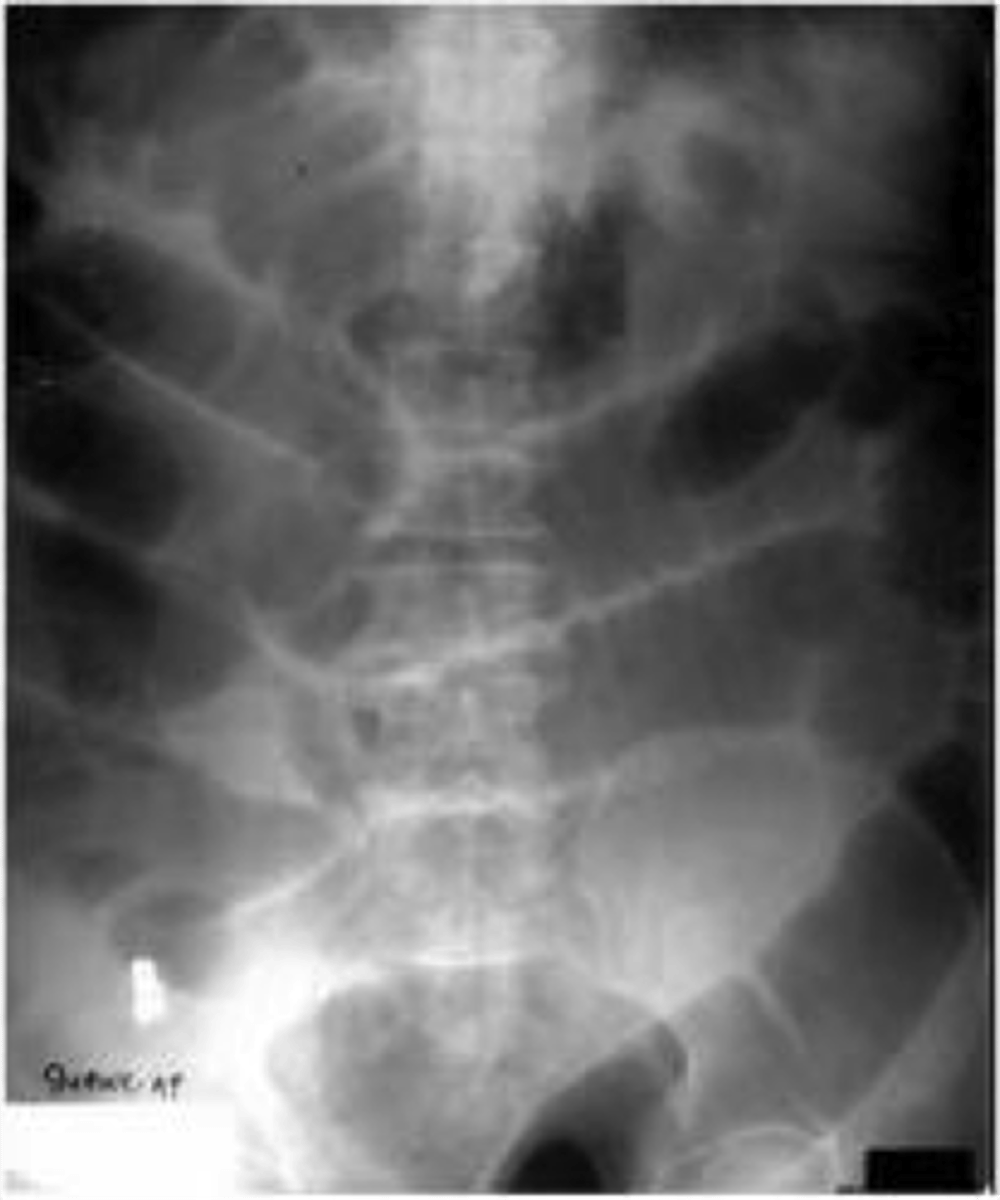

if a pt has "tinkling" sounds on PE, what would you expect to see on XR?

small bowel obstruction → dilated loops of small bowel and air fluid levels

also paralytic ileus has tinkling

if a patient has "tinkling" sounds and peristaltic rushes on PE, which dx do you suspect?

acute paralytic ileus → XR shows diffuse gas filled loops of small and large bowel